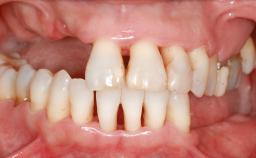

A 45-year-old woman with a completely edentulous maxilla was referred to evaluate the possibility of rehabilitation with an implant-supported prosthesis. This patient was healthy and a non-smoker. She had been wearing a maxillary complete denture opposing a natural mandibular dentition since her twenties. This situation had resulted in progressive resorption of the alveolar ridge, repeatedly creating a need for relining the denture. Twenty years later, despite multiple adaptations and the use of “glues” the denture was unstable and causing the patient psychological and functional discomfort.

| Bone Volume | Deficient vertically or deficient vertically AND horizontally |